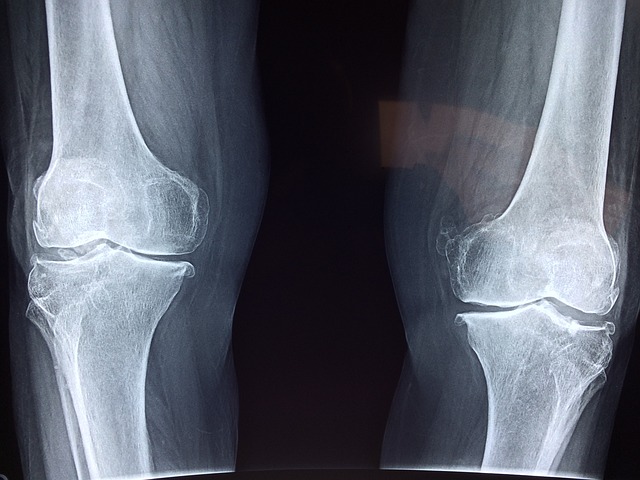

통풍을 진단하기 위해서는 몇 가지 검사를 시행합니다:

- 혈액 검사: 혈중 요산 수치를 측정하여 고요산혈증 여부를 확인합니다.

- 소변 검사: 소변을 통해 요산 배출량을 확인합니다.

- 관절액 검사: 관절에서 체액을 채취하여 요산 결정 유무를 확인합니다.

정기적인 검사를 통해 요산 수치를 모니터링하는 것이 중요합니다. 통풍 증상이 없더라도 고요산혈증이 있는 경우 통풍 발작의 위험이 높아지기 때문입니다.